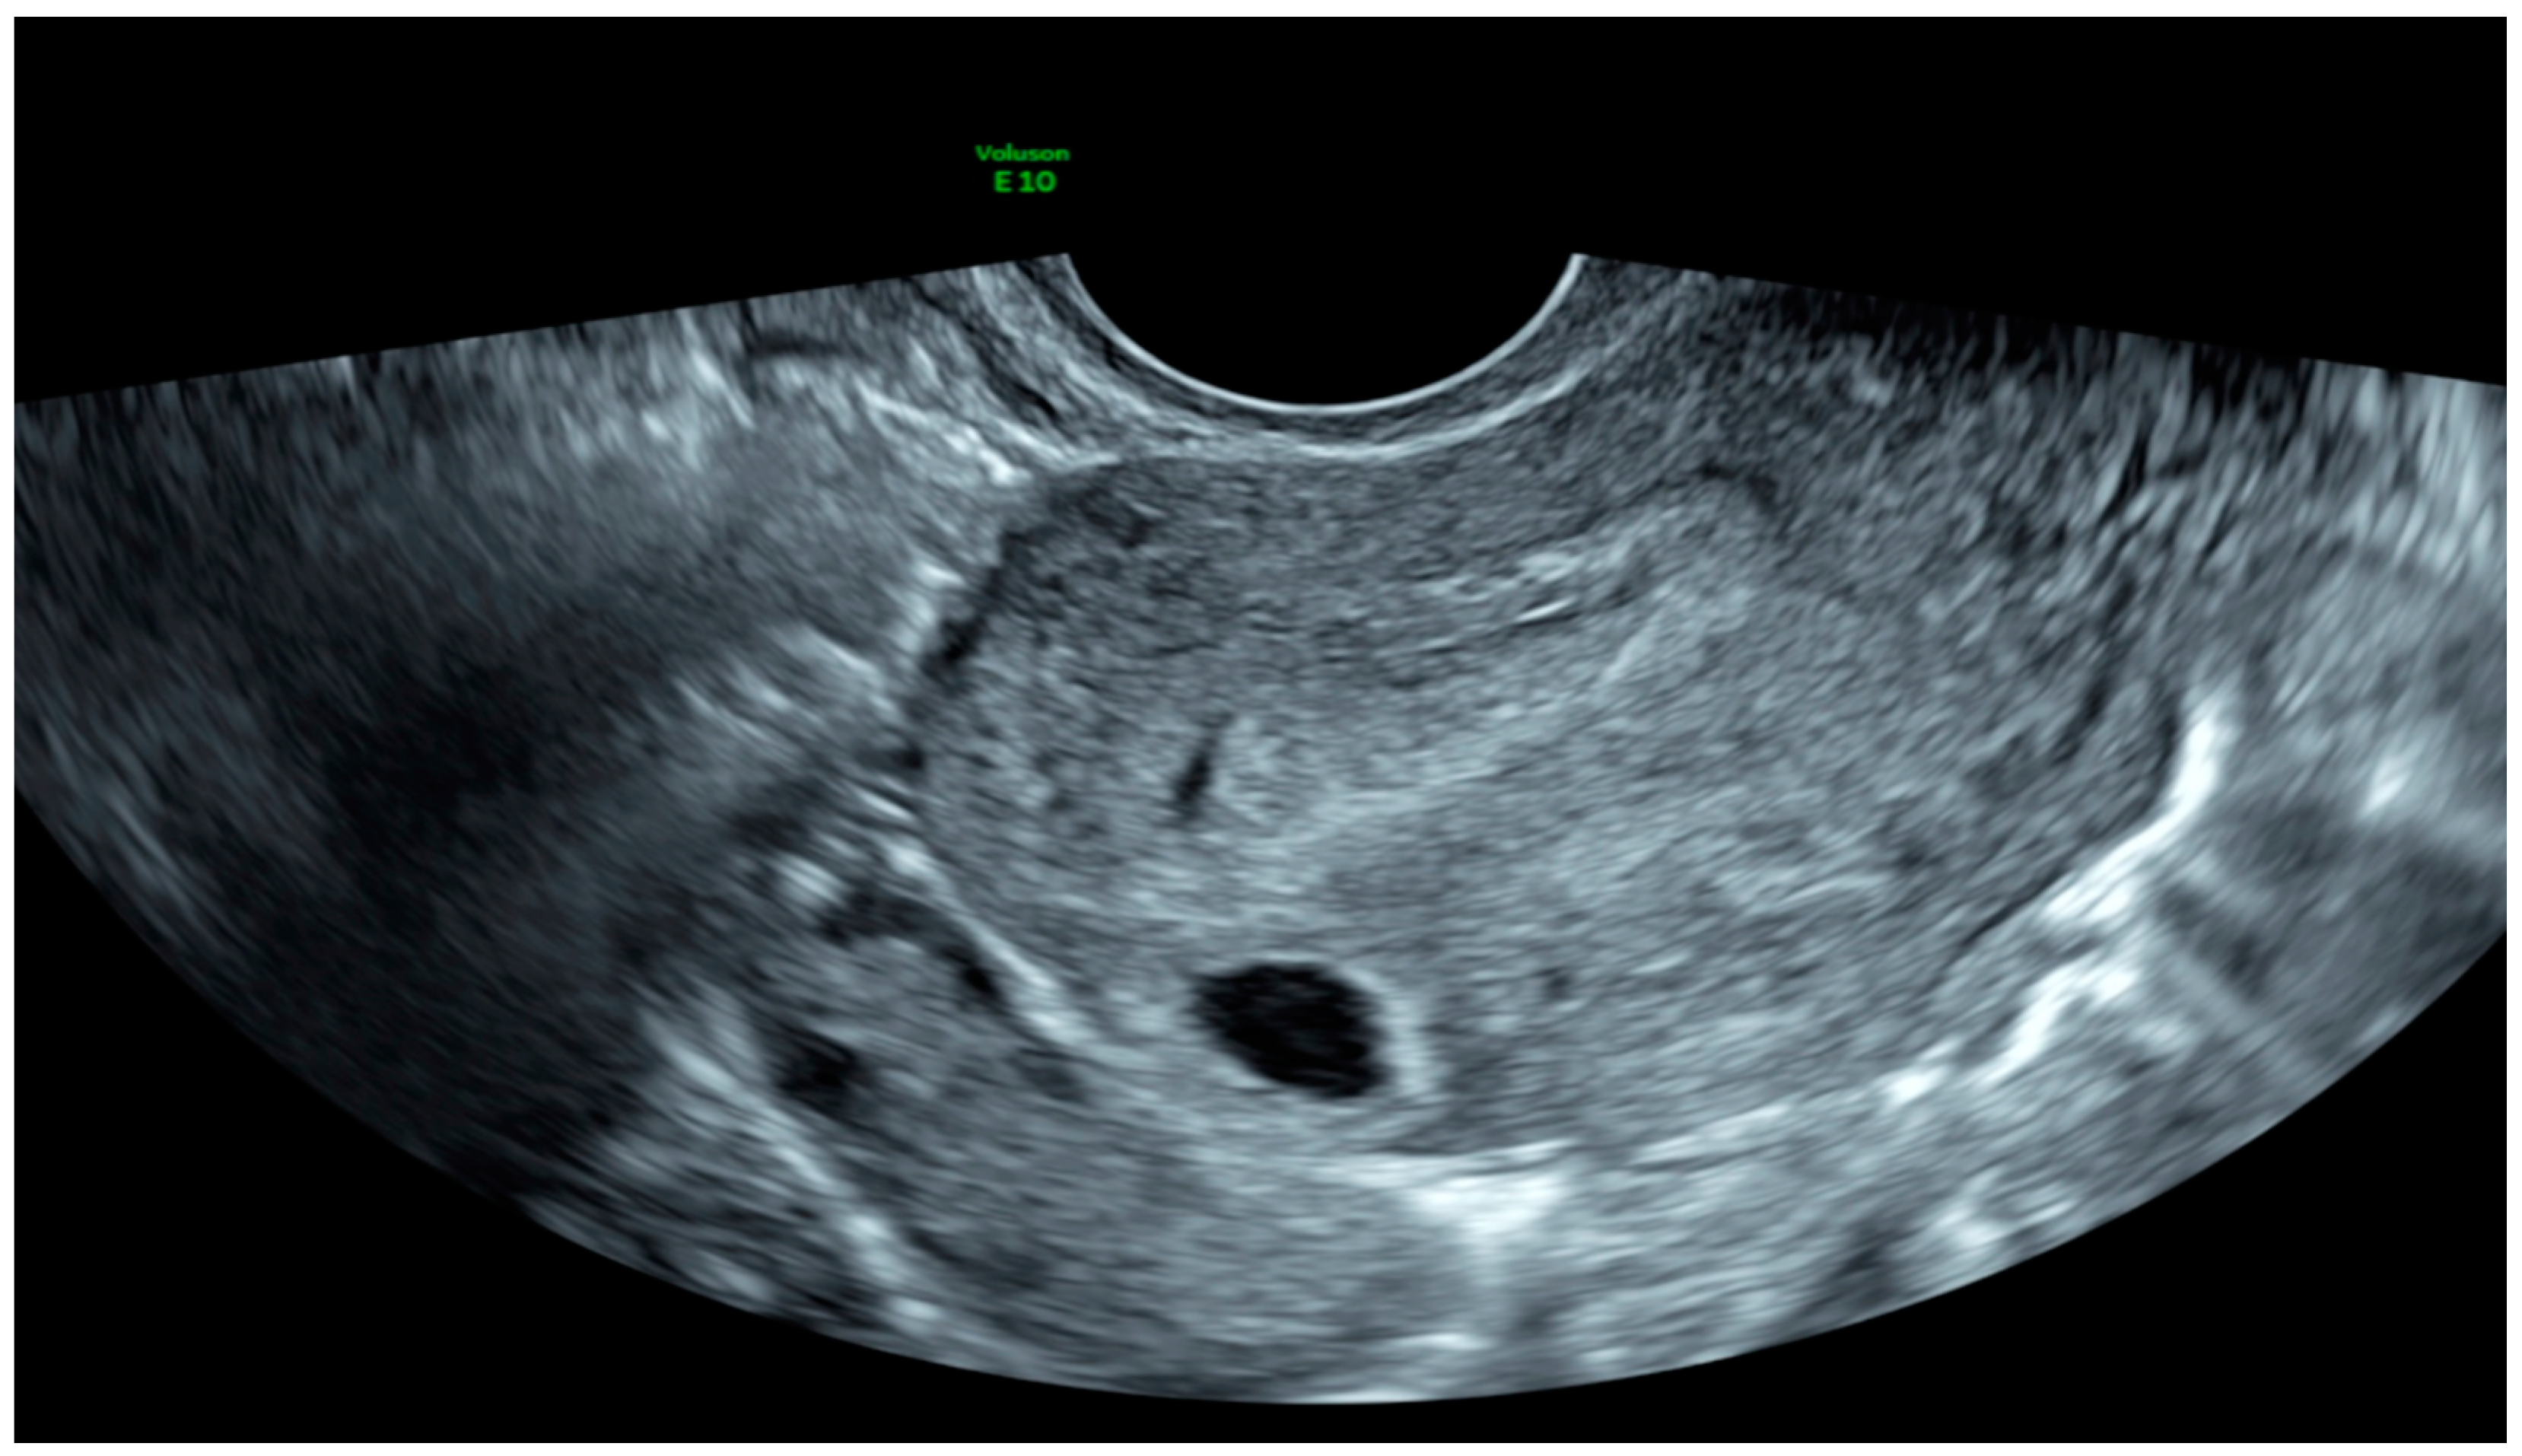

| Case 1 | Asymptomatic | 12 + 1 | 97,388 | GS 78 × 60 mm; with embryo | Radical surgical treatment (LPS hysterectomy + bilateral salpingectomy + uterine arterial embolization + bilateral ureteral stent placement) | Complete resolution |

| Case 2 | Asymptomatic | 6 + 6 | 10,862 | GS 20 × 19 mm; with embryo | Hys: 1st step: CP resection by twizzle; IC Foley catheter 2nd step: vessels electrocoagulation by bipolar twizzle | Reoperation (hys) due to tissue residues and cervical laceration Complete resolution |

| Case 3 | Asymptomatic | 5 | 9747 | GS 20 × 22 mm; no embryo | MTX IM 50 mg/m2 of body surface + Hys | Complete resolution Currently pregnant (PMA Homologous) |

| Case 4 | Brownish vaginal discharge | 6 + 6 | 55,951 | GS 30 × 10 mm; no embryo | Hys | Complete resolution |

| Case 5 | Vaginal bleeding | 9 | 1331 | GS 4.7 × 5 mm; no embryo | Mifepristone 600 mg orally + Misoprostol 400 mcg + MTX IM 50 mg/m2 of body surface | Complete resolution |

| Case 6 | Vaginal bleeding | 6 | 4274 | GS 5.4 × 5 mm with embryo | MTX IM 50 mg/m2 of body surface + Hys: CP resection by twizzle | Complete resolution |

| Scar pregnancy | ||||||

| Case 1 | Asymptomatic | 6 | 119,900 | GS 14 × 16 mm | MTX IM 50 mg/m2 of body surface + Misoprostol 200 µg rectal + Hys (two times) + Curettage | Complete resolution |

| Case 2 | Asymptomatic | 6 + 2 | 31,647 | GS 12 × 10 mm | Mifepristone 600 mg + Misoprostol 400 mcg + Hys: reseptoscopy | Complete resolution |

| Case 3 | Asymptomatic | 7 + 1 | 131,000 | GS 9 × 10 mm | Hys: twizzle and minireseptor + Curettage | Complete resolution |